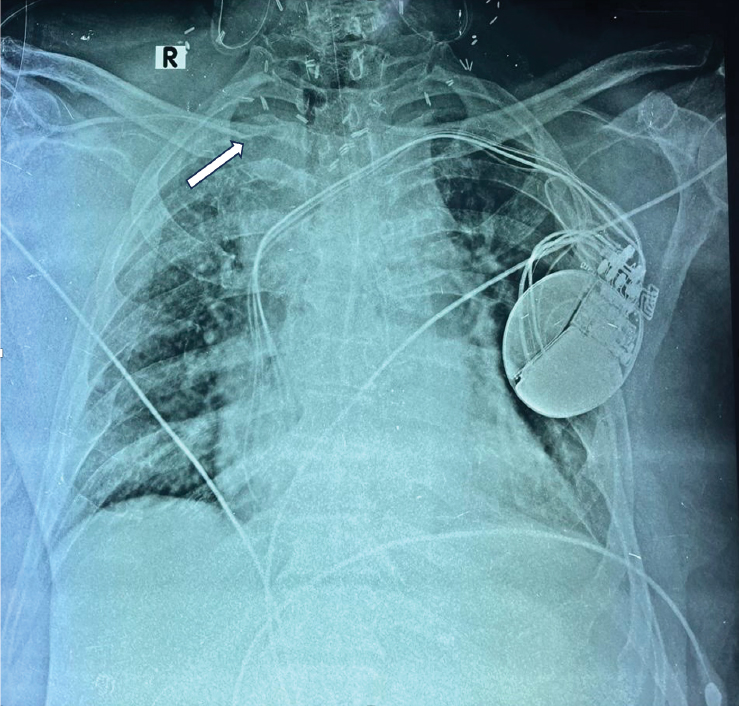

hold and a neck radiograph was ordered immediately. The radiograph revealed

that the central line had malpositioned and its tip was seen at the level of

clavicle in the radiograph, probably lying in the subcutaneous space (Fig. 2).

As a consequence of this, intravenous fluid being given to the patient had been

leaking into surrounding tissues – the same was appearing in the surgical drain

as well as causing local edema. There was no evidence of any mediastinal

Figure 2. Radiograph taken on postoperative day 2 after

noting intravenous propofol appearing in surgical drain showing catheter

malposition (white arrow).